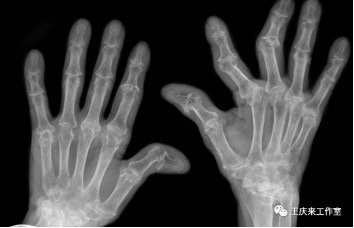

04辅助检查

类风湿关节炎患者类风湿因子阳性率达75%,骨关节炎患者的类风湿因子呈阴性。

另外抗环瓜氨酸抗体检测也有助于类风湿性关节炎的诊断。也可以根据关节B超、放射线检查等对诊断做出帮助。

当然,并不是说类风湿因子阳性就一定得了类风湿性关节炎,这需要医生进行综合分析判断。